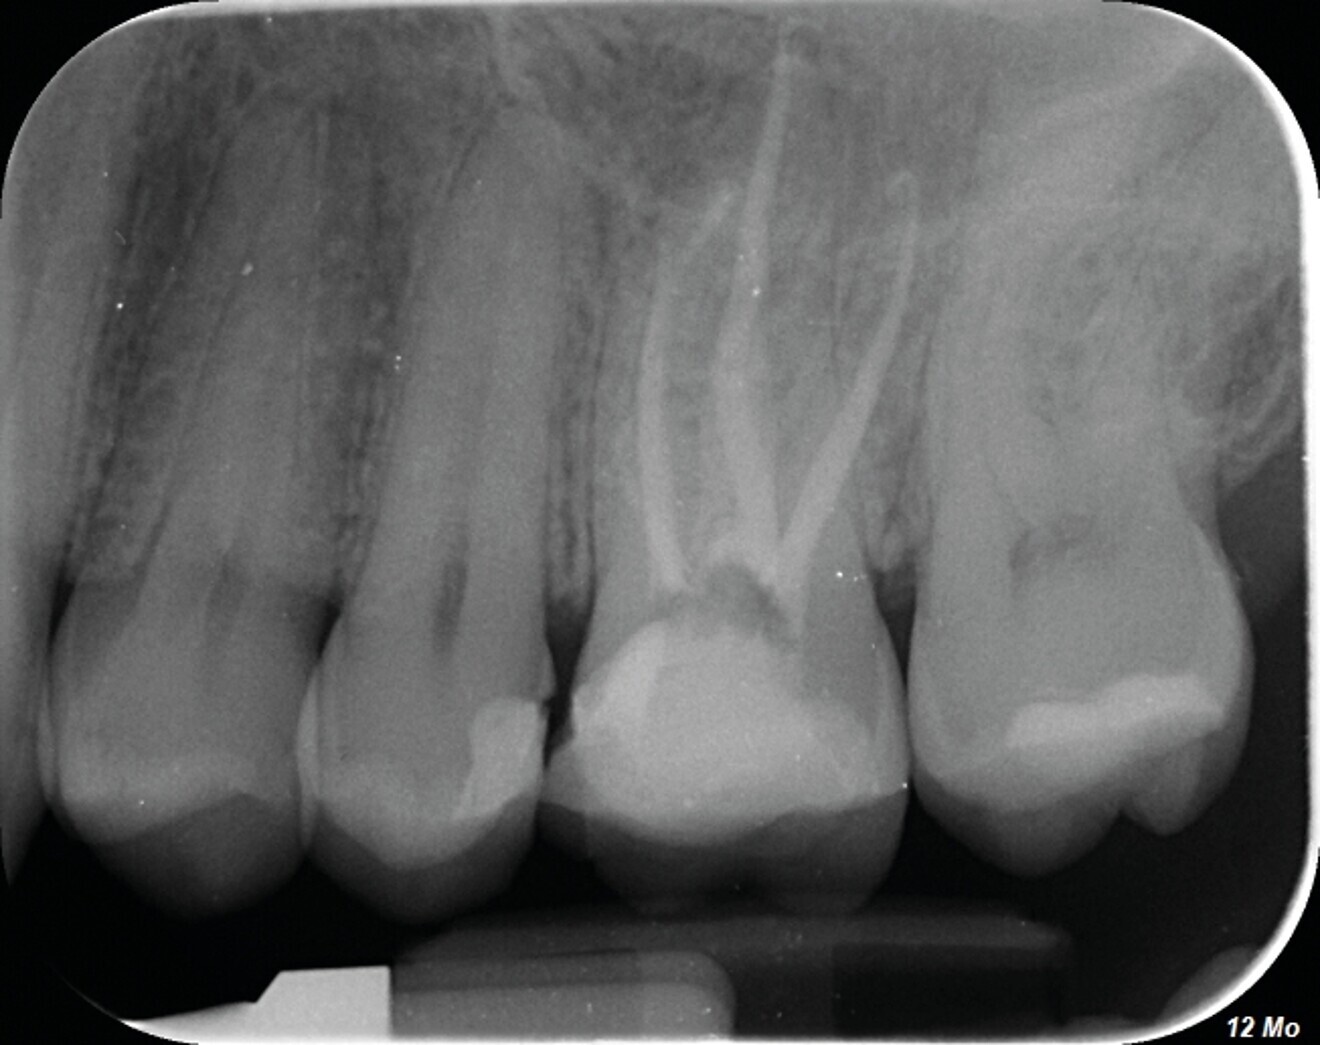

Avec la désinfection et l’obturation du système canalaire, nous ne faisons que rétablir un contexte biologique favorable à la cicatrisation parodontale et à la régénération osseuse (Figs. 1a–c).

Fig. 1c : La radiographie de contrôle à un an, confirme l’efficacité du traitement par la régénération osseuse.